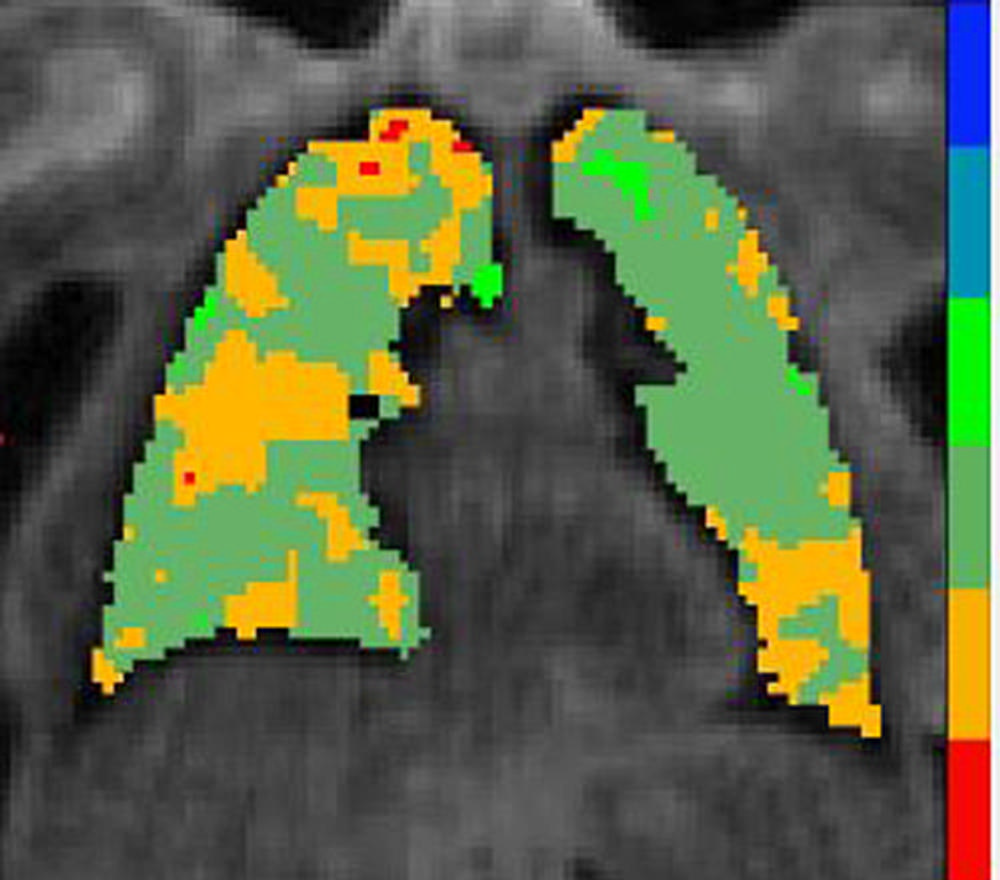

Figure 5. Gas exchange map - Low

High-res (TIF) version

Figure 2. Individuals in the study are plotted with x-axis being rank of pulmonary gas exchange. The black dots show the pulmonary gas exchange ratio, which in this case is the red blood cell to tissue plasma ratio (RBC:mem), on the left y-axis and the blue dots are the cognition scores on the right y-axis. Gas exchange maps of three representative patients from a low, medium and high pulmonary gas exchange.